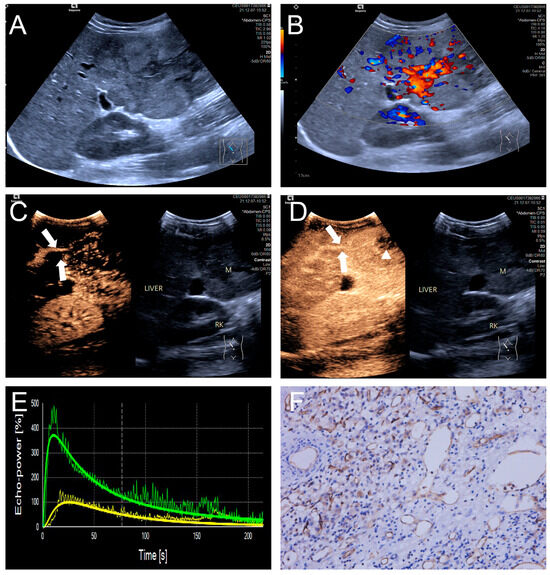

3.3. Qualitative CEUS Performance of HB Lesions: High and Low MVD Groups

Penetrating vessels were significantly more frequent in the high MVD group (p < 0.05). In contrast, no significant differences were observed between the two groups regarding enhancement uniformity or enhancement order (p > 0.05). Representative CEUS features are illustrated in Figure 3 and Figure 4, and the comparative results are summarized in Table 4.

Figure 4.

(A–F) A male patient aged 10 years and 6 months with HB and high MVD. (A) The imaging revealed a lesion with unclear margins and hyperechoic echogenicity in the liver’s left lobe; (B) During the enhancement phase, CDFI revealed abundant vascular signals within the tumor tissue, classified as grade III by Adler; (C,D) The CEUS exhibited non-uniform enhancement progressing from periphery to center, with non-enhancing regions (triangles) within the lesion and peripheral penetrating vessels (arrows); (E) TIC curves showed contrast enhancement of the lesion (green) and perfusion of the adjacent liver parenchyma (yellow). Jagged lines indicated raw signal data, and smooth lines indicated the fitted curves; (F) The biopsy specimen’s cytological immunohistochemical staining revealed dense microvessels (CD34 staining × 200), and the MVD measured 42 lines/HPF.